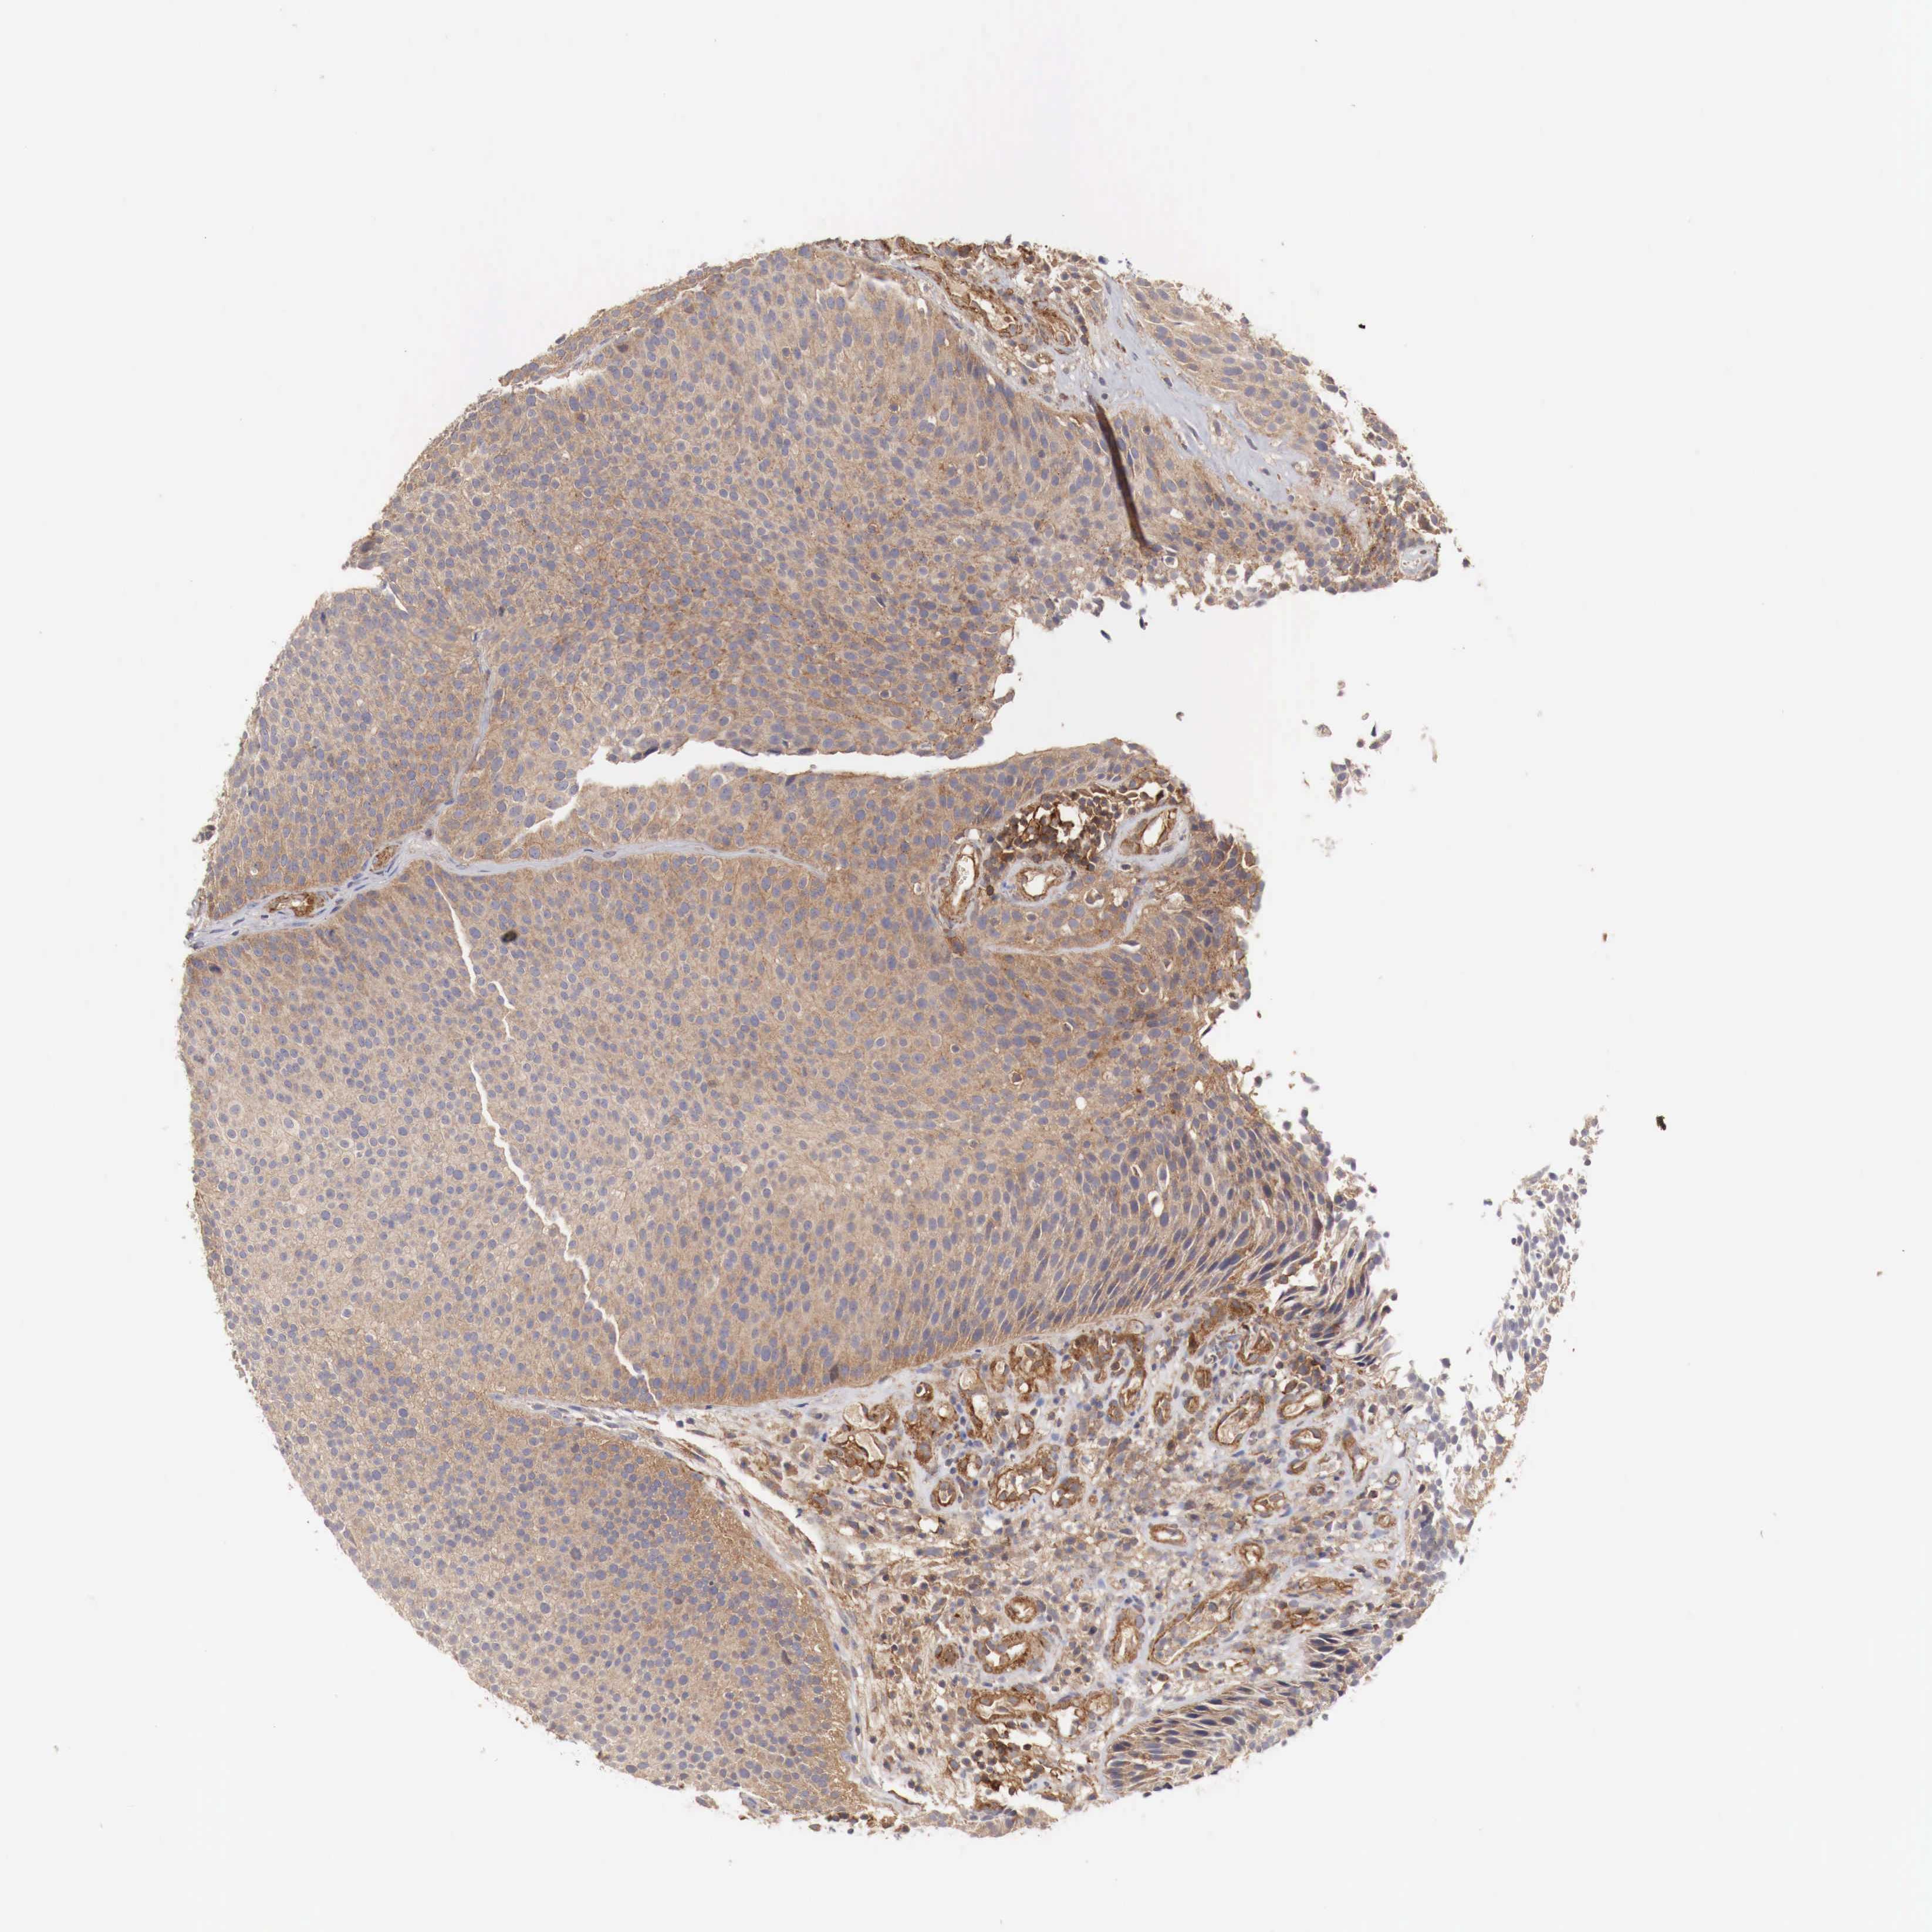

UROTHELIAL CANCER - Protein expressioni

A mouse-over function shows sample information and annotation data. Click on an image to view it in a full screen mode. Samples can be filtered based on level of antibody staining by selecting one or several of the following categories: high, medium, low and not detected. The assay and annotation is described here.

Antibody stainingi

Antibody staining in the annotated cell types in the current human tissue is reported as not detected, low, medium, or high, based on conventional immunohistochemistry profiling in selected tissues. This score is based on the combination of the staining intensity and fraction of stained cells.

Each image is clickable and will lead to virtual microscopy that enables deeper exploration of all samples and also displays staining intensity scores, fraction scores and subcellular localization as well as patient and tissue information for each sample.

Antibody HPA000429

Staining

High

Medium

Low

Not detected

Intensity

Strong

Moderate

Weak

Negative

Quantity

>75%

75%-25%

<25%

None

Location

Nuclear

Cytoplasmic/membranous

Cytoplasmic/membranous,nuclear

Urothelial carcinoma, Low grade